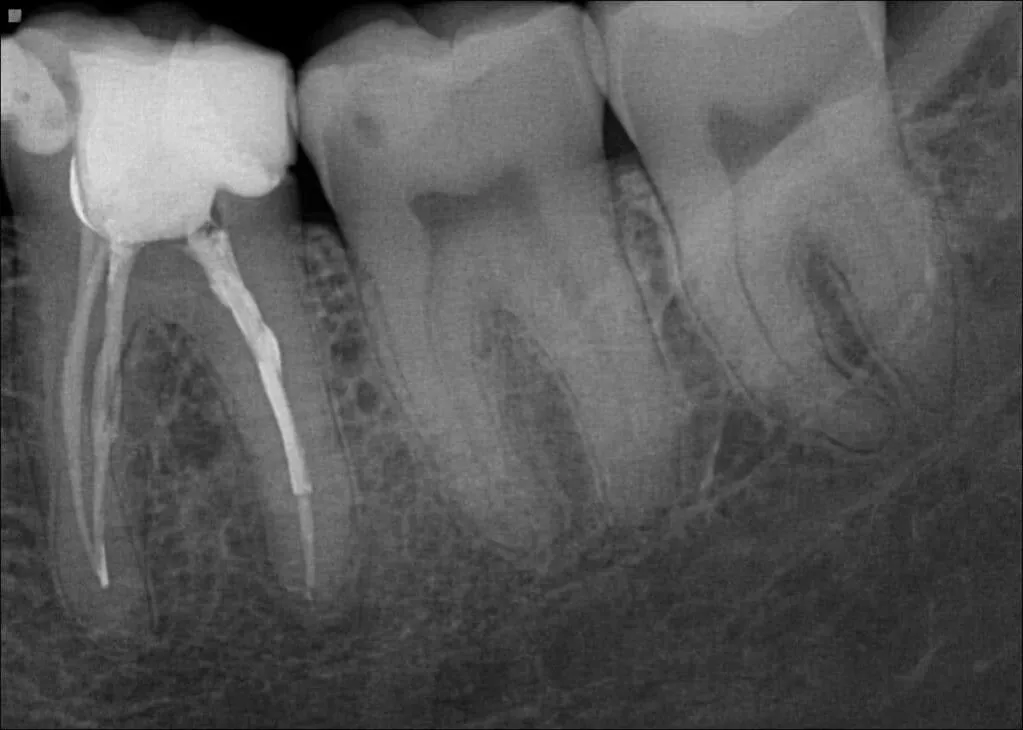

Zdjęcie RTG punktowe: jak prześwietlenie demaskuje ukryte problemy?

Zdjęcie RTG punktowe, zwane również wewnątrzustnym, to podstawowe narzędzie w diagnostyce bólu zęba. Jest to małe zdjęcie, które obejmuje jeden lub dwa zęby wraz z otaczającą je kością. Jest ono absolutnie niezbędne, ponieważ pozwala mi zobaczyć rzeczy, które są niewidoczne podczas badania klinicznego:

- Stan korzenia: Czy nie ma zmian w jego budowie, czy nie ma resorpcji (zaniku tkanki).

- Kość wokół zęba: Czy nie ma stanów zapalnych okołowierzchołkowych, które na zdjęciu wyglądają jak ciemne plamy wokół wierzchołka korzenia.

- Próchnica na powierzchniach stycznych: Często rozwija się ona między zębami i jest niewidoczna podczas oględzin.

- Próchnica pod wypełnieniami: Stare, nieszczelne plomby mogą ukrywać rozwijającą się próchnicę wtórną.

- Stan wypełnień kanałowych: Jeśli ząb był już leczony kanałowo, mogę ocenić jakość tego leczenia.

Dzięki zdjęciu RTG punktowemu mogę precyzyjnie zlokalizować źródło problemu i zaplanować odpowiednie leczenie. Jest to badanie o minimalnej dawce promieniowania, a korzyści diagnostyczne są nieocenione.